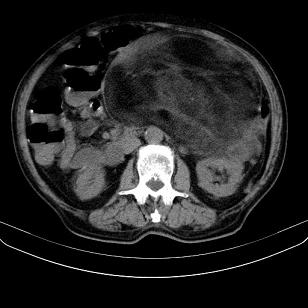

标题: CT21671:男,88岁,左上腹包块 [打印本页]

标题: CT21671:男,88岁,左上腹包块

患者因咳嗽而住院,自觉右上腹包块,无其他不适。